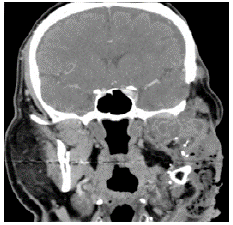

A contrasted CT scan of the neck and paranasal sinuses was performed, identifying a mass involving the left mandibular region and the pterigopalatine fossa with associated bone destruction; a biopsy with histopathological study report was also performed, showing follicular and plexiform ameloblastoma. Taking into account the findings of the tomography and the reports from the pathologist, ameloblastoma was diagnosed without a doubt. Extension studies were also performed with chest CT and cervical lymph node puncture biopsy, ruling out distant disease. The case was discussed during a multidisciplinary meeting where a left partial mandibulectomy, mandibular condyle reconstruction with plaque and fibula free flap were established as management. The pathology of the surgical specimen showed tumor-free edges and surgical margins of 10mm (Figure 1).

Histopathology of mandibulectomy with evidence of follicular ameloblastoma and odontogenic epithelial islands with peripheral columnar cells.

Figure 1: Histopathology of mandibulectomy with evidence of follicular ameloblastoma and odontogenic epithelial islands with peripheral columnar cells.

Source: Document obtained during the study.